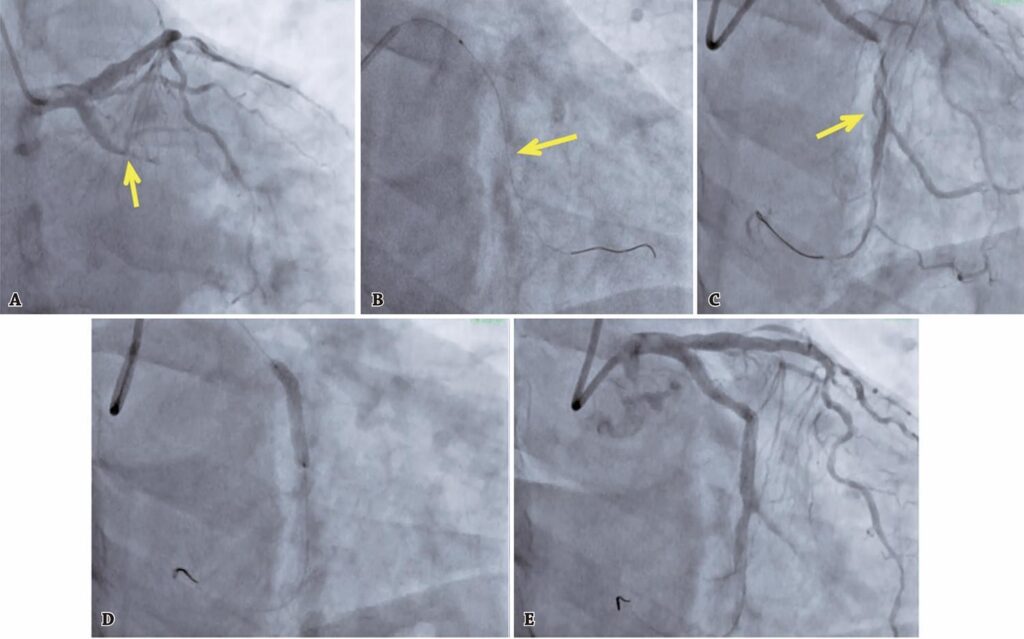

Vários fatores, incluindo intervenções terapêuticas aprimoradas e tecnologias avançadas, levaram a melhores desfechos clínicos nas intervenções coronárias percutâneas complexas. No entanto, ainda podem ocorrer complicações capazes de impactar negativamente na sobrevida do paciente e nos custos de saúde. O risco dessas complicações pode ser reduzido, por meio de operadores experientes e procedimentos preventivos. Este artigo discute uma série de casos de cinco pacientes com problemas específicos relacionados aos procedimentos, como perfuração coronária, dissecções, fechamento abrupto das coronárias e fenômeno de no-reflow .